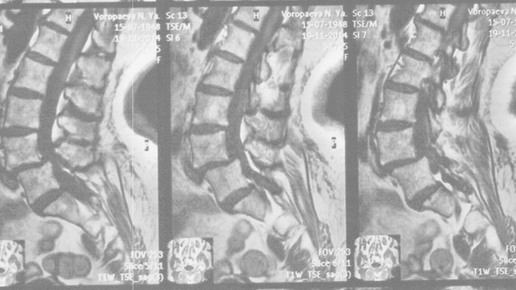

Наличие на снимках позвоночника «спондилолистеза» (антелистеза, ретролистеза, бокового листеза) является одним из безусловных признаков межпозвонковых (межпозвоночных) грыж в сегменте со спондилолистезом. Чтобы было понятнее, что это такое, попробуем сравнить позвоночник с колонной из кубиков, контуры которой плавно огибают грани этих кубиков, без выступов кубика над кубиком. Это в норме. При «спондилолистезе»  плавность этих линий нарушается, на снимках явственно наблюдается их ломаный изгиб, напоминающий очертания "лестничной ступеньки"...

Спондилолистез. Что это такое? Почему возникает? Возможно, в заключении вашего МРТ значится: «спондилолистез» или «антелистез» или «ретролистез позвонка. Что это такое❓Каковы причины этого состояния❓ ◽️Спондилолистез — это смещение одного позвонка относительно соседних. Позвонок, как звено цепи под названием позвоночник, покидает свое нормальное место и “соскальзывает” кпереди или кзади. Такое ненормальное положение позвонка может приводить к боли в спине и симптомам в ногах и руках: боли, онемении и слабости. Что заставляет позвонки смещаться❓ Силы, которые воздействуют на позвонок, приводят к его сдвигу, если окружающие структуры не обеспечивают стабильное положение позвонка:  - Межпозвонковые диски теряют упругость при возрастном износе и позволяют позвонкам смещаться (дегенеративный спондилолистез); - Дужка позвонка ломается под воздействием ежедневных нагрузок и больше не удерживает тело позвонка на месте (истмический спондилолистез); - Имеется врожденная аномалия развития позвонка, способствующая его смещению (диспластический спондилолистез); - При грубой травме (дтп, падение с высоты и т.д.) ломается позвонок, разрываются связки, разрывается межпозвонковый диск, и все это приводит к смещению позвонка (травматический спондилолистез); - Такие заболевания, опухоль позвонка или его воспаления, приводят к потере стабильности позвоночника и смещению позвонков (патологический спондилолистез); - После непродуманной и слишком травматичной операции на позвоночнике нарушается устойчивое положение позвонка и он смещается (ятрогенный спондилолистез). В зависимости от выраженности симптомов и причины спондилолистеза лечение будет различаться 🙌🏻. Для подбора наиболее эффективного лечения в вашем случае (в Санкт-Петербурге) приглашаю на мою бесплатную онлайн-консультацию: ✅ httpdoctorbeliaev.ru